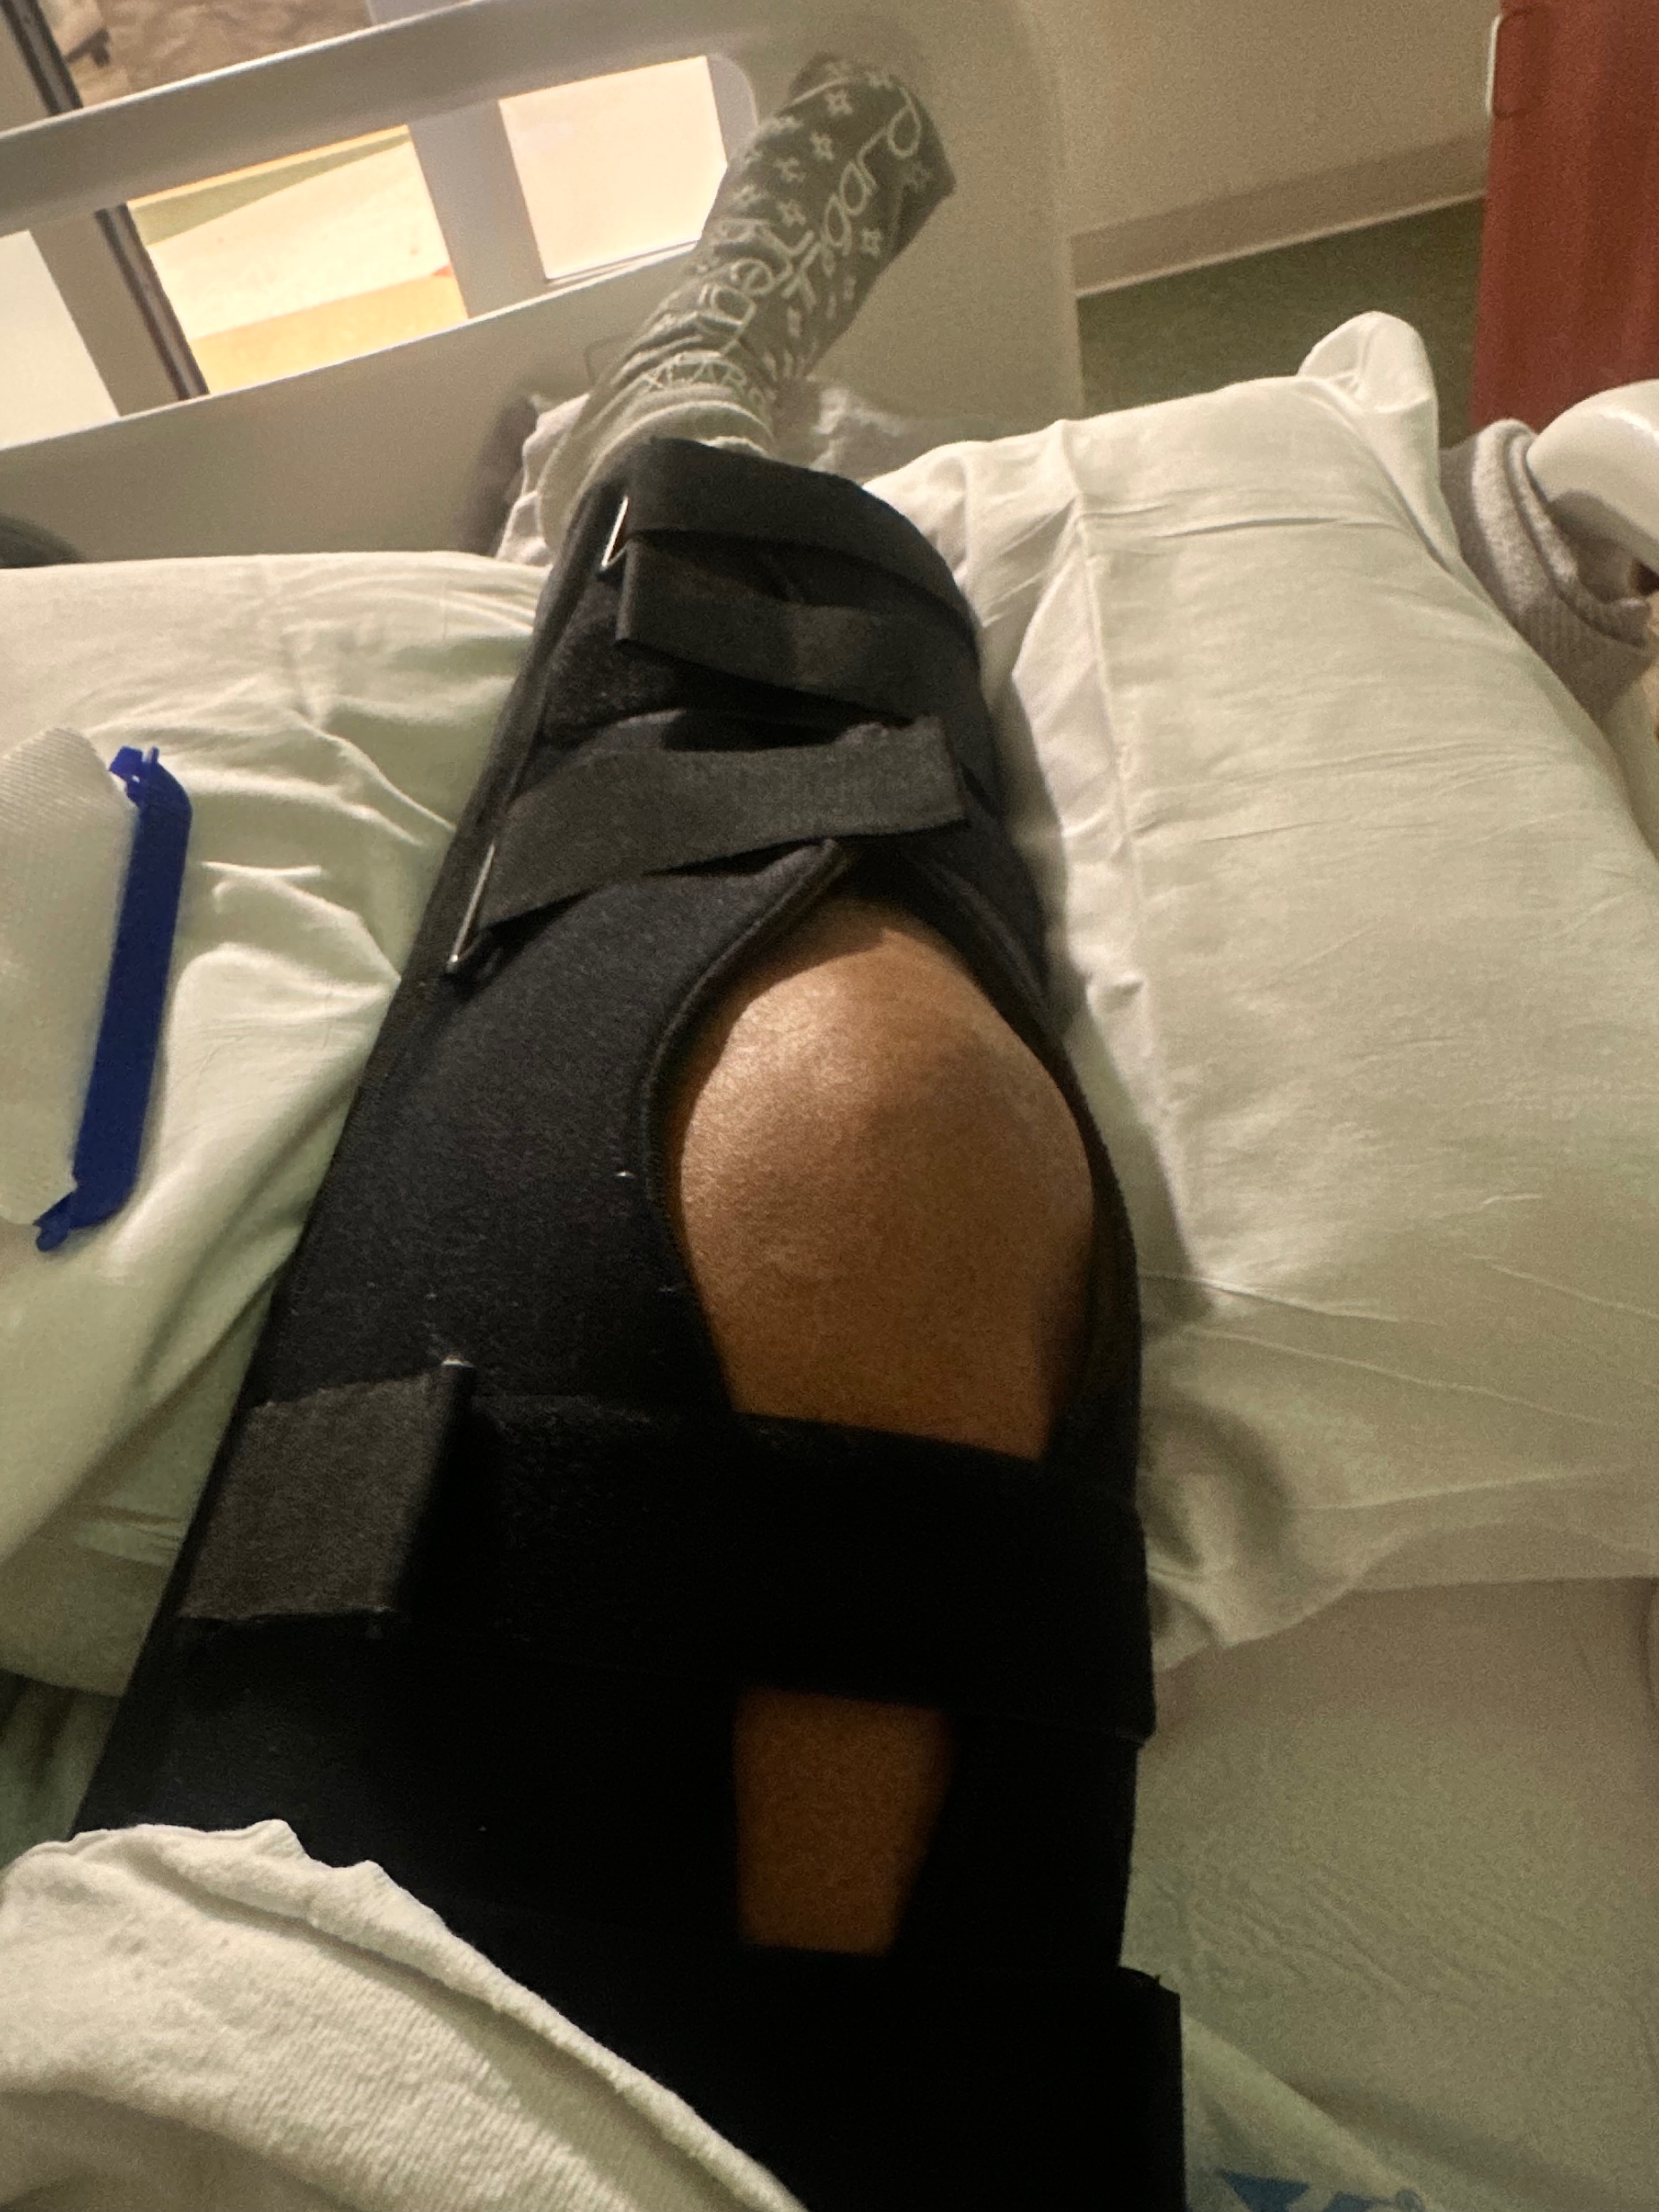

• I cannot straighten my leg

• I cannot walk or bear weight

• I have lost mobility, independence, and muscle function

• I am at serious risk of permanent disability